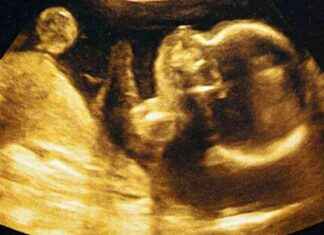

Bebeklerin doğmadan önce tatları ayırt edebildiği ortaya çıktı! Yapılan araştırma, miniklerin lahana ve havuç gibi sebzelerin tatlarına nasıl tepki verdiğini gözler önüne serdi. Bu buluş, anne adaylarının beslenme tercihlerini yeniden değerlendirmesine neden olabilir. İşte...